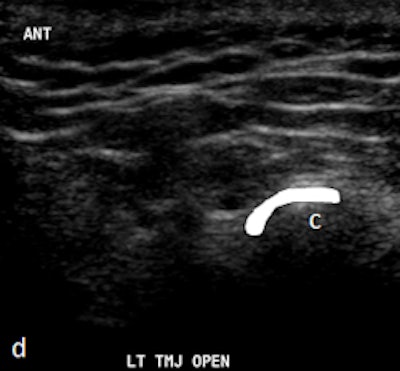

Dr. Friedman prefers that patients be supine on a stretcher with the jaw tilted away from the side to be examined. Then the person performing the ultrasound palpates the joint while the patient opens and closes her mouth. Gel is then placed on the joint, and the probe is placed at various positions around the joint. The images are examined to determine whether there is anterior displacement of the disk while the joint is the closed-mouth position.

"If the ultrasound is abnormal, the patient should be referred for an MRI, and any patient scheduled for surgery also must have an MRI," he said. "The main challenge is learning to detect what is normal on ultrasound. We also acknowledge that abnormal anteromedial and medially displaced disks may be missed or misinterpreted with ultrasound."